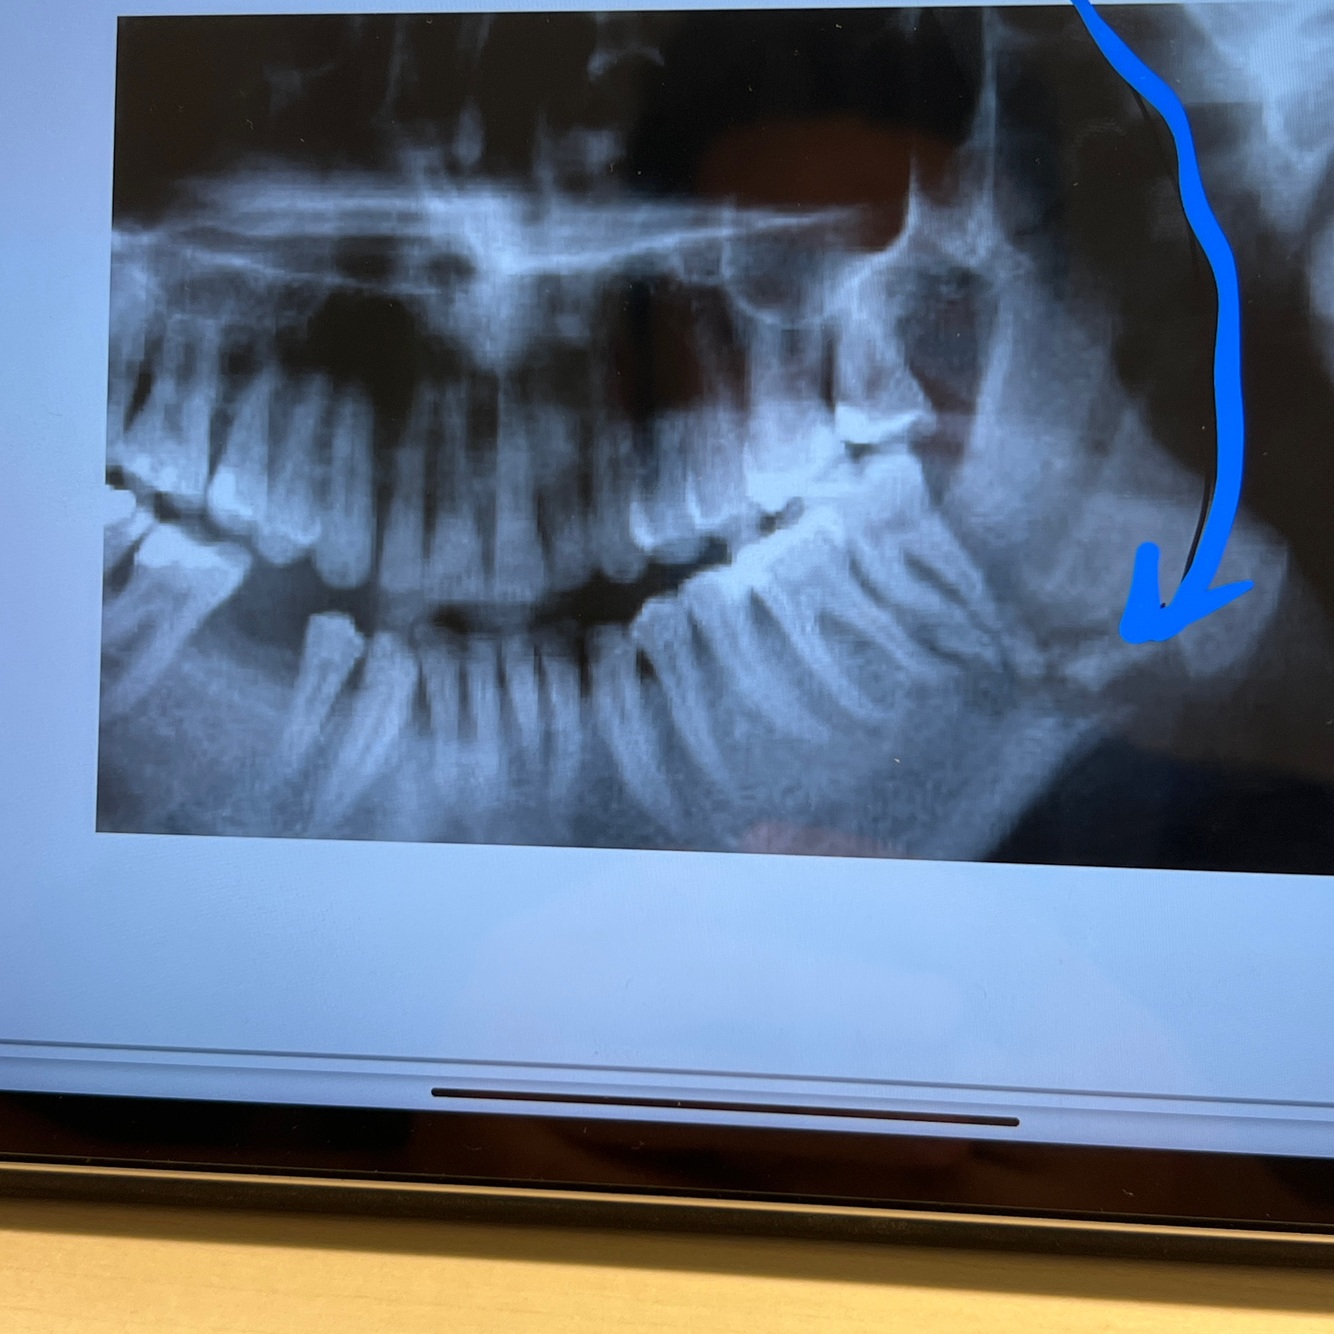

Garre sort Xray feature .? Mostly happen in … disease . Bone mass is … and can be calcified and has ….

•On an X-ray we can often discover a tooth with caries on the opposing side of where the hard bone structure can be found. • homogenous and has a thin but pronounced cortical bone surrounding it •Mostly in JUVENILES Key : joobe nisll جوب نيل charactristic by rigid bone